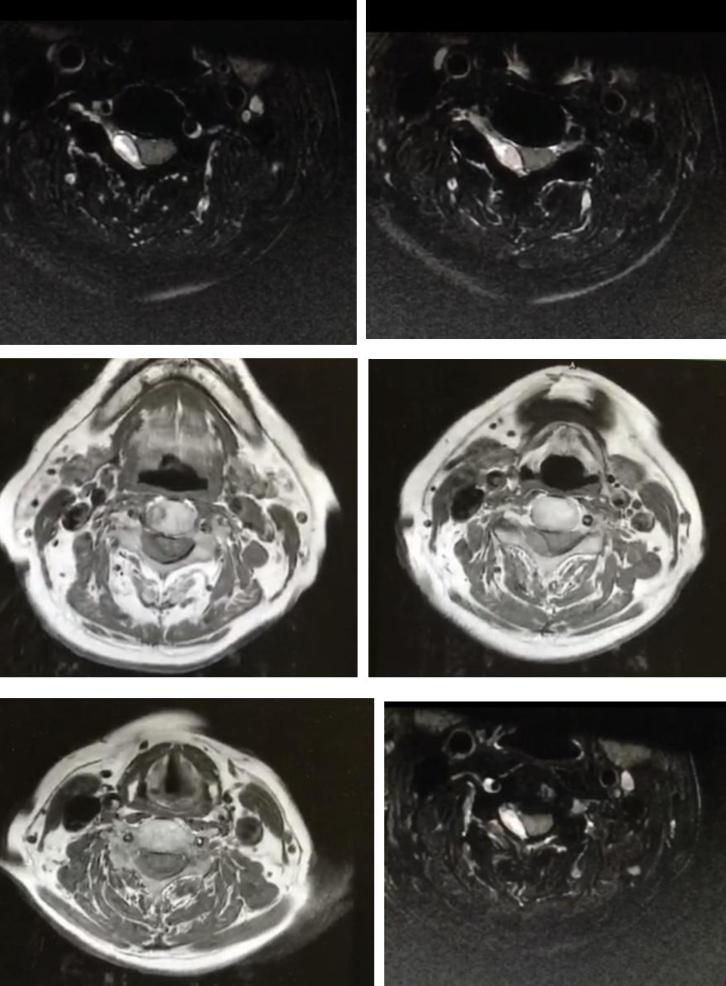

男性68岁,四肢末梢麻木2月余,伴有站立不稳,加重1周,不能独立行走。查体双侧跟膝胫试验欠稳准,双侧位置觉、震动觉减退。

答案:脊髓亚急性联合变性。患者老年男性,亚急性病程,以深感觉受累为主要表现,脊髓影像长节段病灶,轴位显示后索病灶“圆点征”,颅内影像改变无特异性,NMOSD相关抗体检测以及OB均阴性。其特征性影像有“圆点征”、“小字征”、“三角征”、“八字征”等。

男性11岁,进行性左下肢无力9年。患者于2岁时“哮喘发作”后4天出现左下肢无力。

答案:哮喘性肌萎缩(asthmaticamyotrophy)、Hopkins综合征(Hopkinssyndrome),又称急性哮喘并发脊髓灰质炎样损害。是一种罕见的疾病,多以脊髓前角细胞受累为主。临床表现:哮喘急性发作后几天至几周,迅速发生肢体弛缓性下运动神经元瘫痪,多累及单侧肢体,在大多数情况下可进展为患肢严重肌肉萎缩。治疗方面:对皮质类固醇的反应很差,以支持对症治疗为主。

病例12

男,21岁,进行性右侧肢体无力1月。无发热、腹泻等病史。

答案:生殖细胞瘤。颅内生殖细胞瘤多发于儿童和青少年,以10~25岁多见。主要发生于颅内中线位置上,常见于松果体区和鞍区,发生在基底节区和丘脑的约占4%~10%,而松果体区是生殖细胞瘤最好发区。CT平扫为圆形不规则形或蝴蝶形、均匀等或稍高密度、有或无钙化和小囊变;强化可显现较小的囊变,多表现为中度到明显均匀一致的强化,少数不均匀强化。病灶周边有圆点状钙化。松果体区及鞍区同时发现肿瘤病灶则有利于生殖细胞瘤的诊断。MRI扫描多为等或稍长T1、稍长T2信号,偶尔T1混有高信号出血灶。均一强化、边界清楚,仅少数呈中等或不均匀强化。基底节区生殖细胞瘤肿瘤体积较大,但占位效应不明显、瘤旁水肿较轻。增强扫描时表现为不规则花环样强化或斑点样强化。